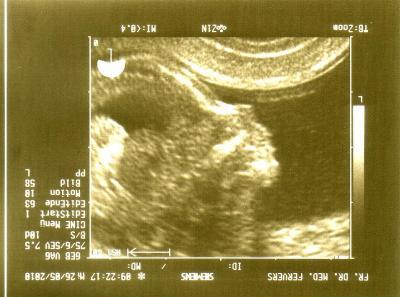

Nachdem ihr alle immer so fleißig von euren Vorsorgeuntersuchungen schreibt, gebe ich auch mal einen kleinen Bericht + Bild ab: Zwerg war bei 15+7 (oder besser 16+0) und anfangs noch schläfrig, hat sich die Augen gerieben. Mit dem Kopf in der einen Ecke, mit den Füßen in der anderen Ecke so weit gestreckt wie (noch) möglich. Das soll sehr gut sein, so kann er keinen Unfug mit der Nabelschnur anstellen. Dann gab es saubere Profilaufnahmen (meine FÄ hat sich richtig doll Mühe gegeben und mir wieder viele Bilder ausgedruckt). Einmal messen: SSL gut 10cm, GL also gut 18cm und als sie dann zwischen die Beinchen gucken wollte, hat der Zwerg den rechten Arm hochgenommen, Hand zum Gesicht, Daumen in den Mund und *schwups* einmal gepflegt auf die Seite gedreht: von wegen zwischen die Beine gucken!!! NÄ! Kind spüren ist witzig: wenn wir spät aufstehen oder ich mal vergesse rechtzeitig etwas zu essen, dann scheint der Kleene mit dem Fruchtwasser zu spielen und ich bekomme Schluckauf. Morgens - vor allem wenn ich ins Büro fahre - pennt er so bis 11h. Und bei fremden Männerstimmen geht das Theater los im Bauch: Kopf links und weicher Druck, Beine rechts und zwickende Fußtritte *thank-you!*.

Bild zu VS letzte Woche / Zwerg2010 zeigt sein Gesicht / Kind spüren - Forum für November - Mamis